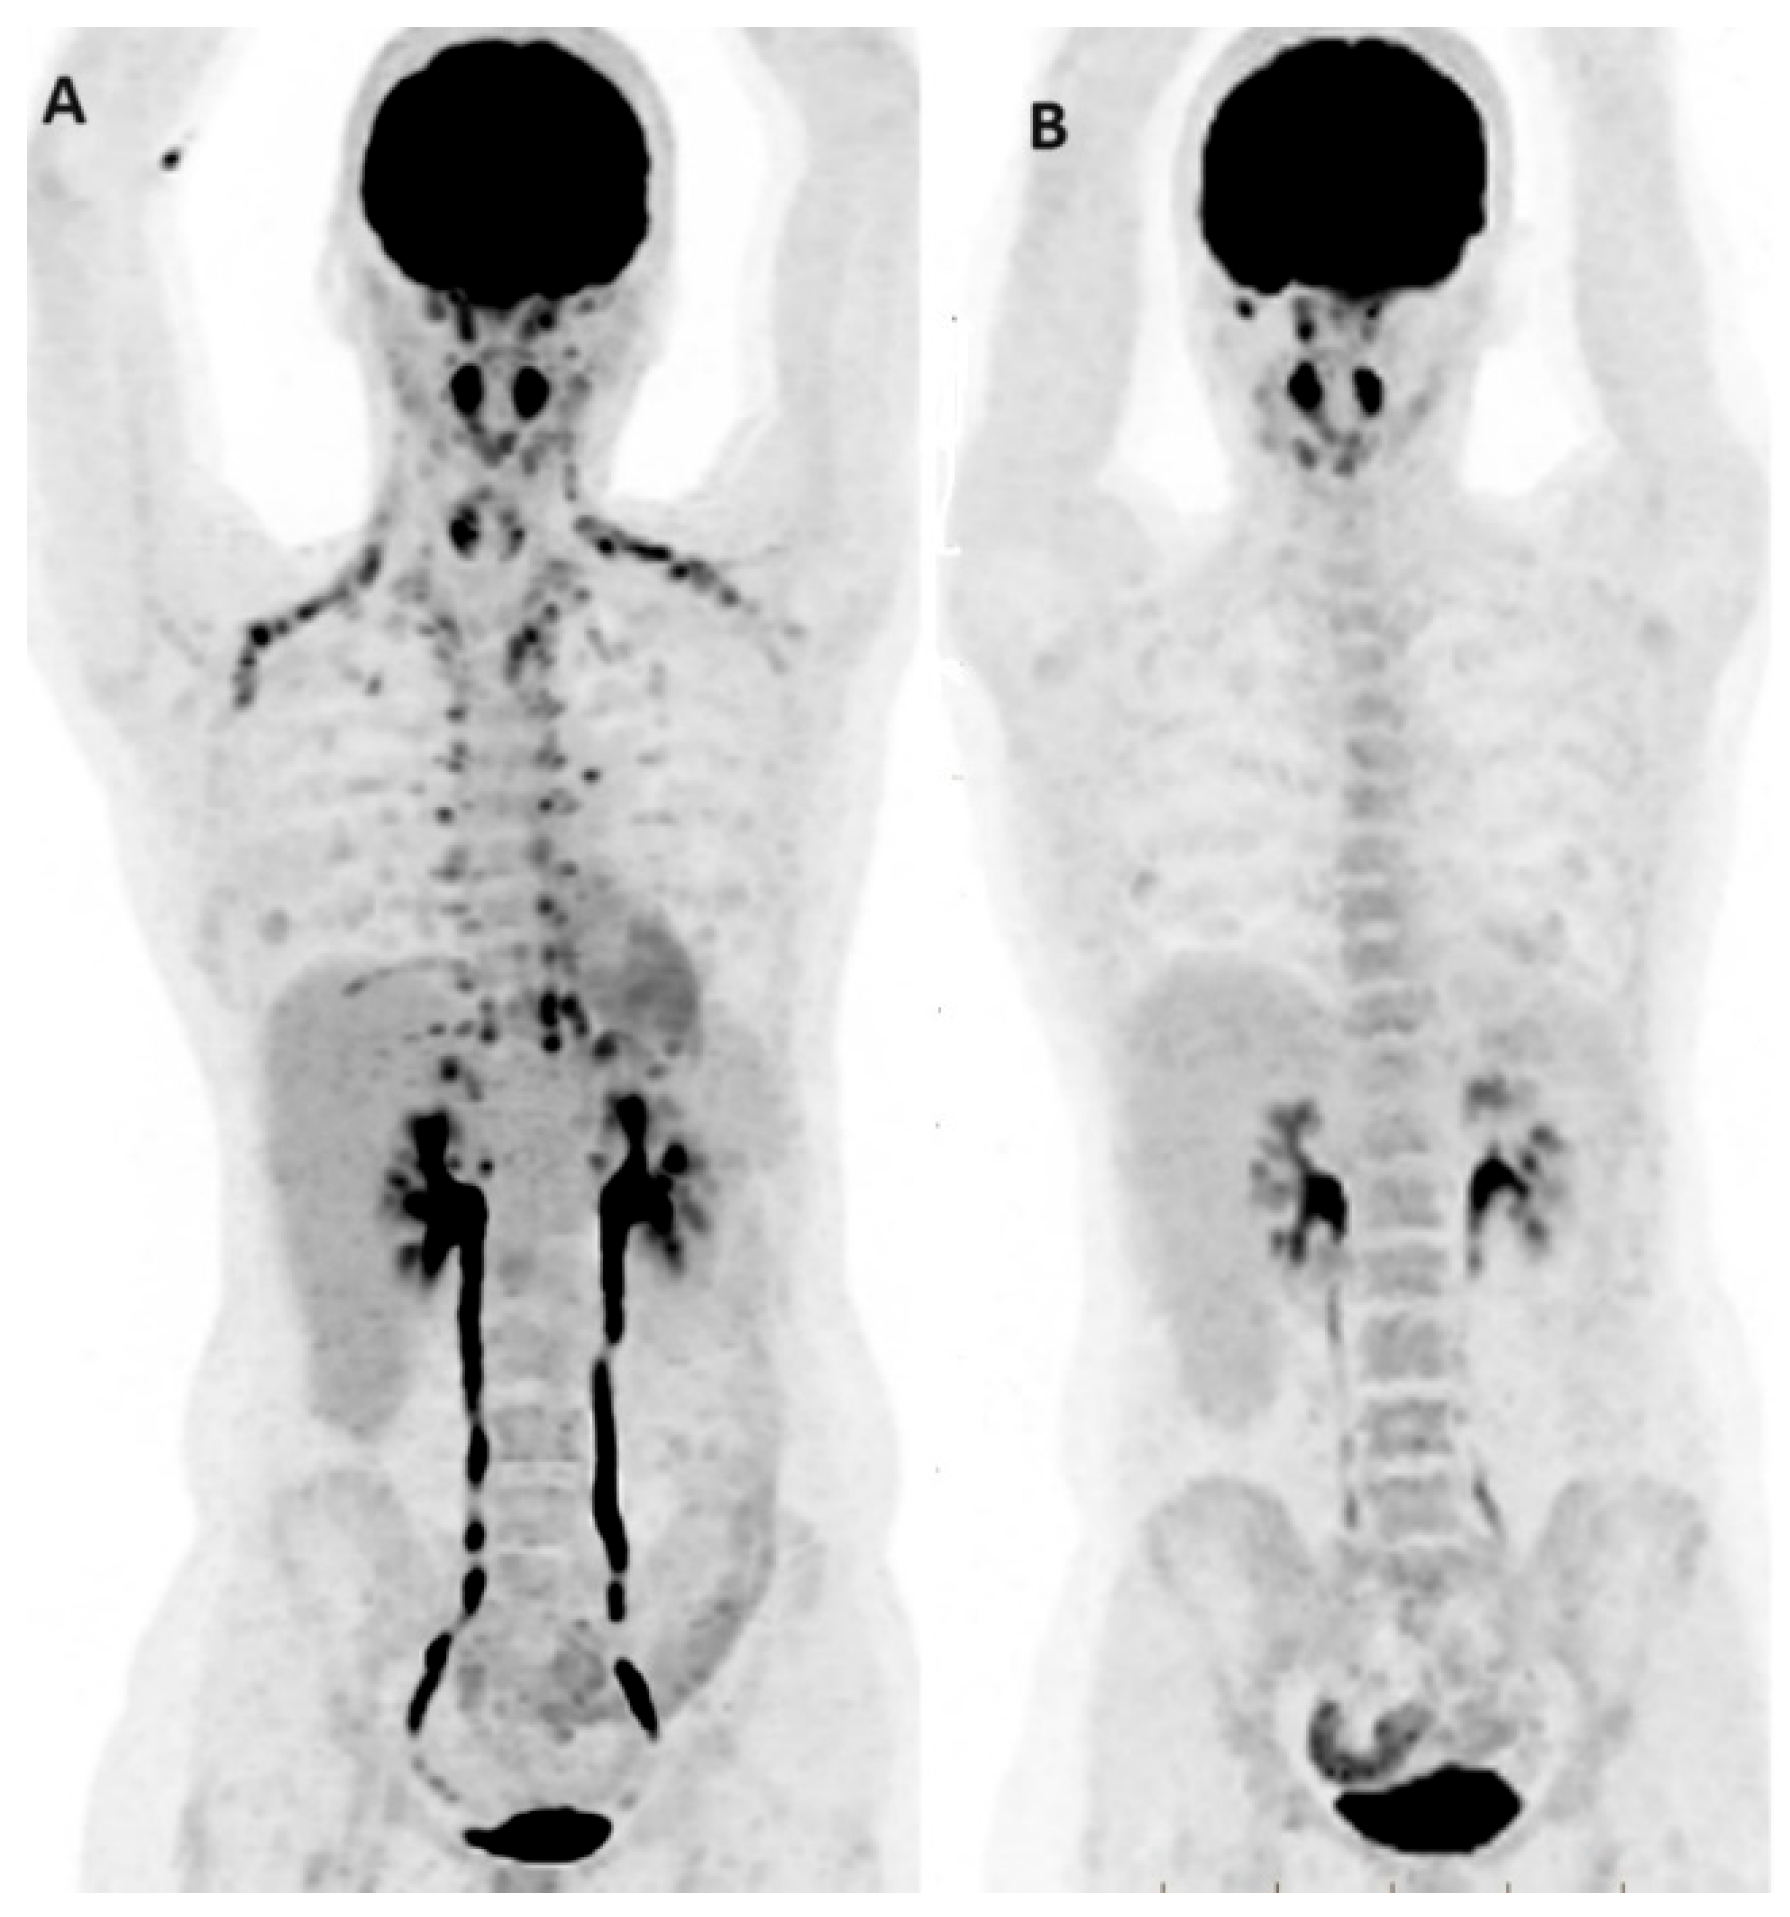

- Hildebrandt, M.G.; Naghavi-Behzad, M.; Vogsen, M. A role of FDG-PET/CT for response evaluation in metastatic breast cancer? Semin. Nucl. Med. 2022, 52, 520–530. [Google Scholar] [CrossRef] [PubMed]

- Suto, H.; Inui, Y.; Okamura, A. Is CT or FDG-PET more useful for evaluation of the treatment response in metastatic HER2-positive breast cancer? A case report and literature review. Front. Oncol. 2023, 13, 1158797. [Google Scholar] [CrossRef] [PubMed]